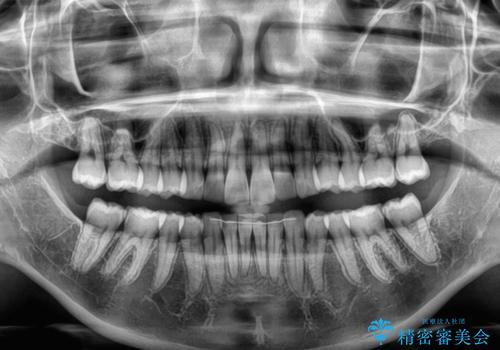

上下左右の親知らずを抜歯し、上下ともに歯列を後方と側方に拡大し、口元を突出させることなくデコボコを解消することとしました。

前歯の形が台形であり、歯列が整ったところでブラックトライアングルが目立つ仕上がりとなったため、IPR(歯と歯の間を削る処置)によって歯の形態を修正し、隙間の目立たない歯列に仕上げることができました。